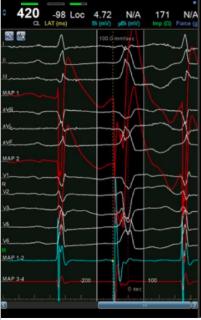

2. 单选题

30 秒

<p>根据室早图形&#xff0c;选出最有可能起源的位置</p>

根据室早图形,选出最有可能起源的位置

LCC

RVT前游离壁&前间隔交界处

三尖瓣环

RVOT后间隔